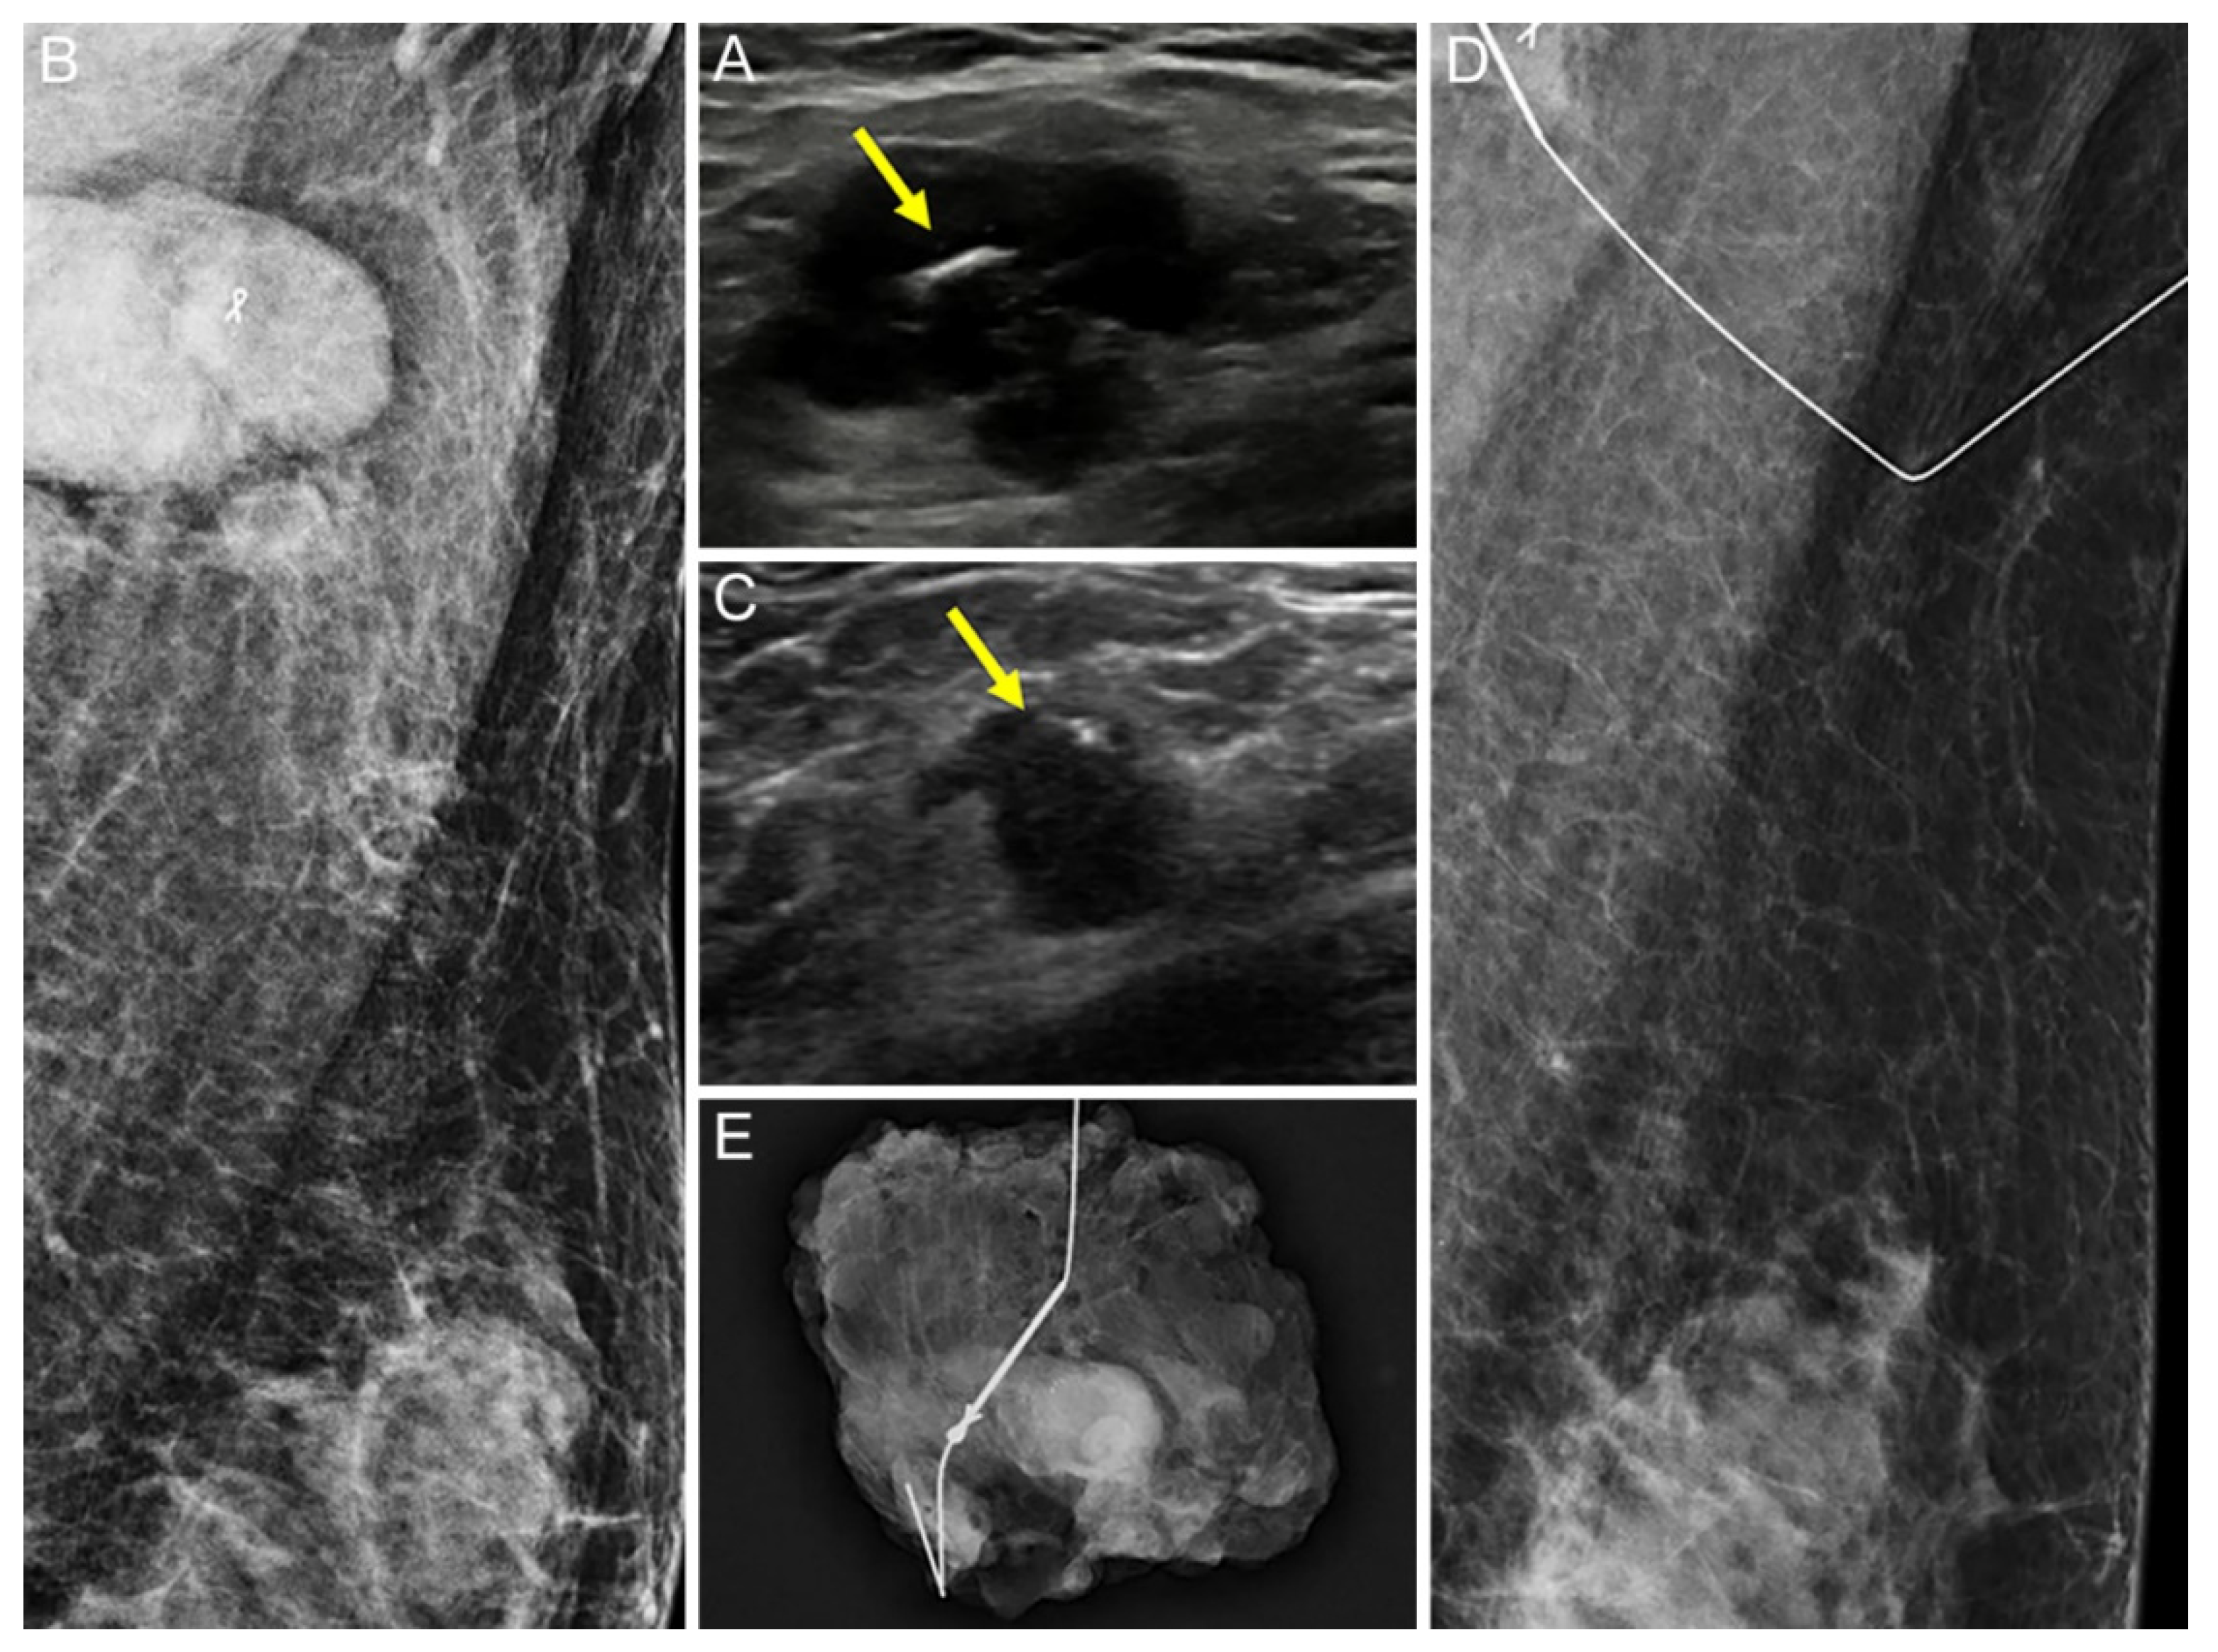

2.2. Tissue Marker Insertion for Axillary Lymph Nodes before NAC

2.3. Localization of Tissue Marker-Inserted Axillary Lymph Nodes after NAC